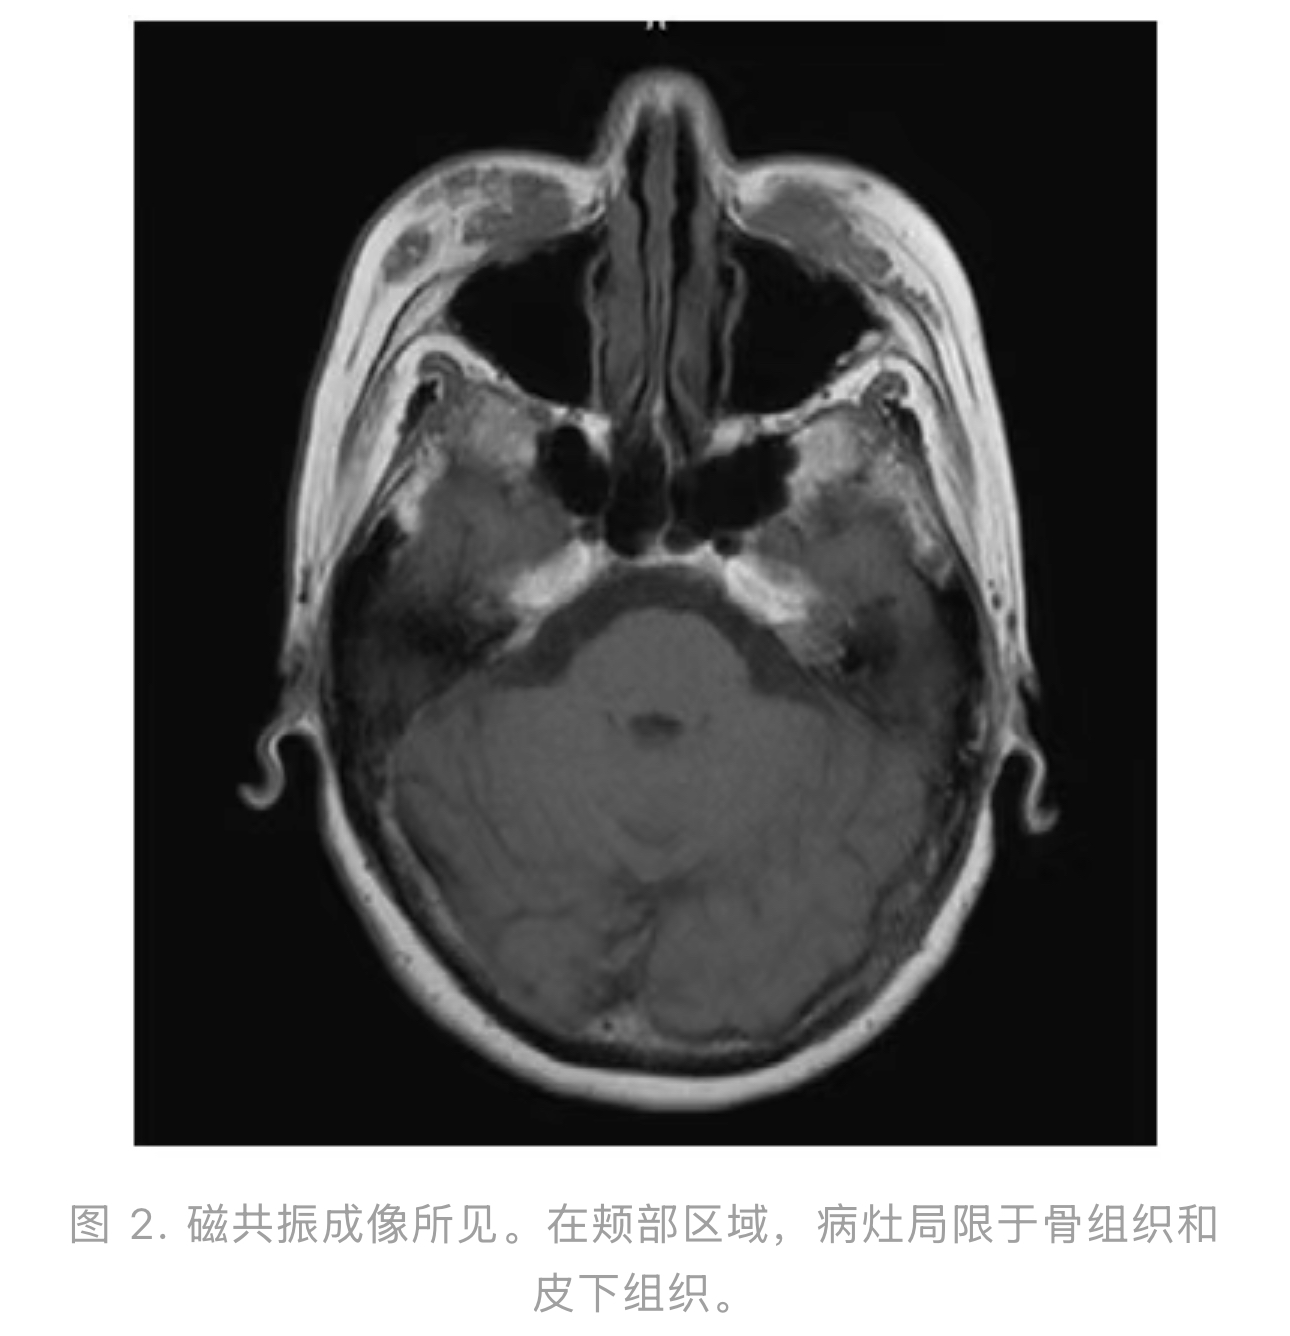

初次检查时,患者皮肤发红,皮下硬结有侵犯皮肤表面的风险(图1)。磁共振成像

结果显示病灶广泛分布,T1加权像上呈稍低信号强度,延伸至下方骨表面(图2)。考虑到皮下硬结可能暴露于皮肤表面,我们决定首先将其切除,然后对由此产生的凹陷性轮廓不规则进行二期重建手术。